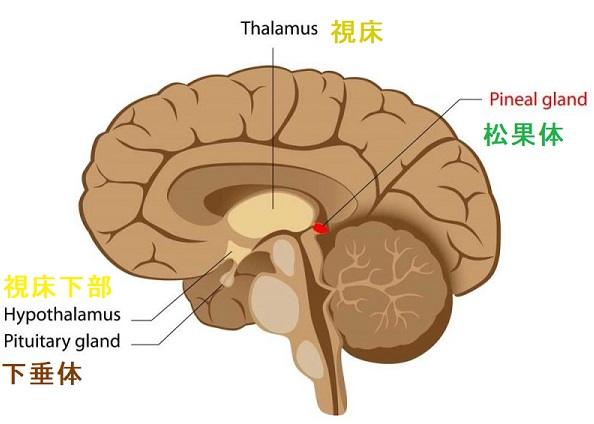

- GnRH(LH-RH)[性腺刺激ホルモン放出ホルモン(Gonadotropin releasing hormone, GnRH)]:は視床下部で合成・分泌され、下垂体前葉からFSHとLHを分泌させます

- MRIで視床下部や下垂体に腫瘍の有無を確認

視床下部過誤腫の治療

視床下部過誤腫の治療、抗てんかん薬・ホルモン療法[LH-RHアナログ,リュープロリン(リュープリン®)投与]は対症療法に過ぎず、根治的には、視床下部過誤腫の摘出しかありません。しかし、視床下部は、脳の最も深い所にあり手術が困難です。手術後、記憶障害の後遺症もあります。